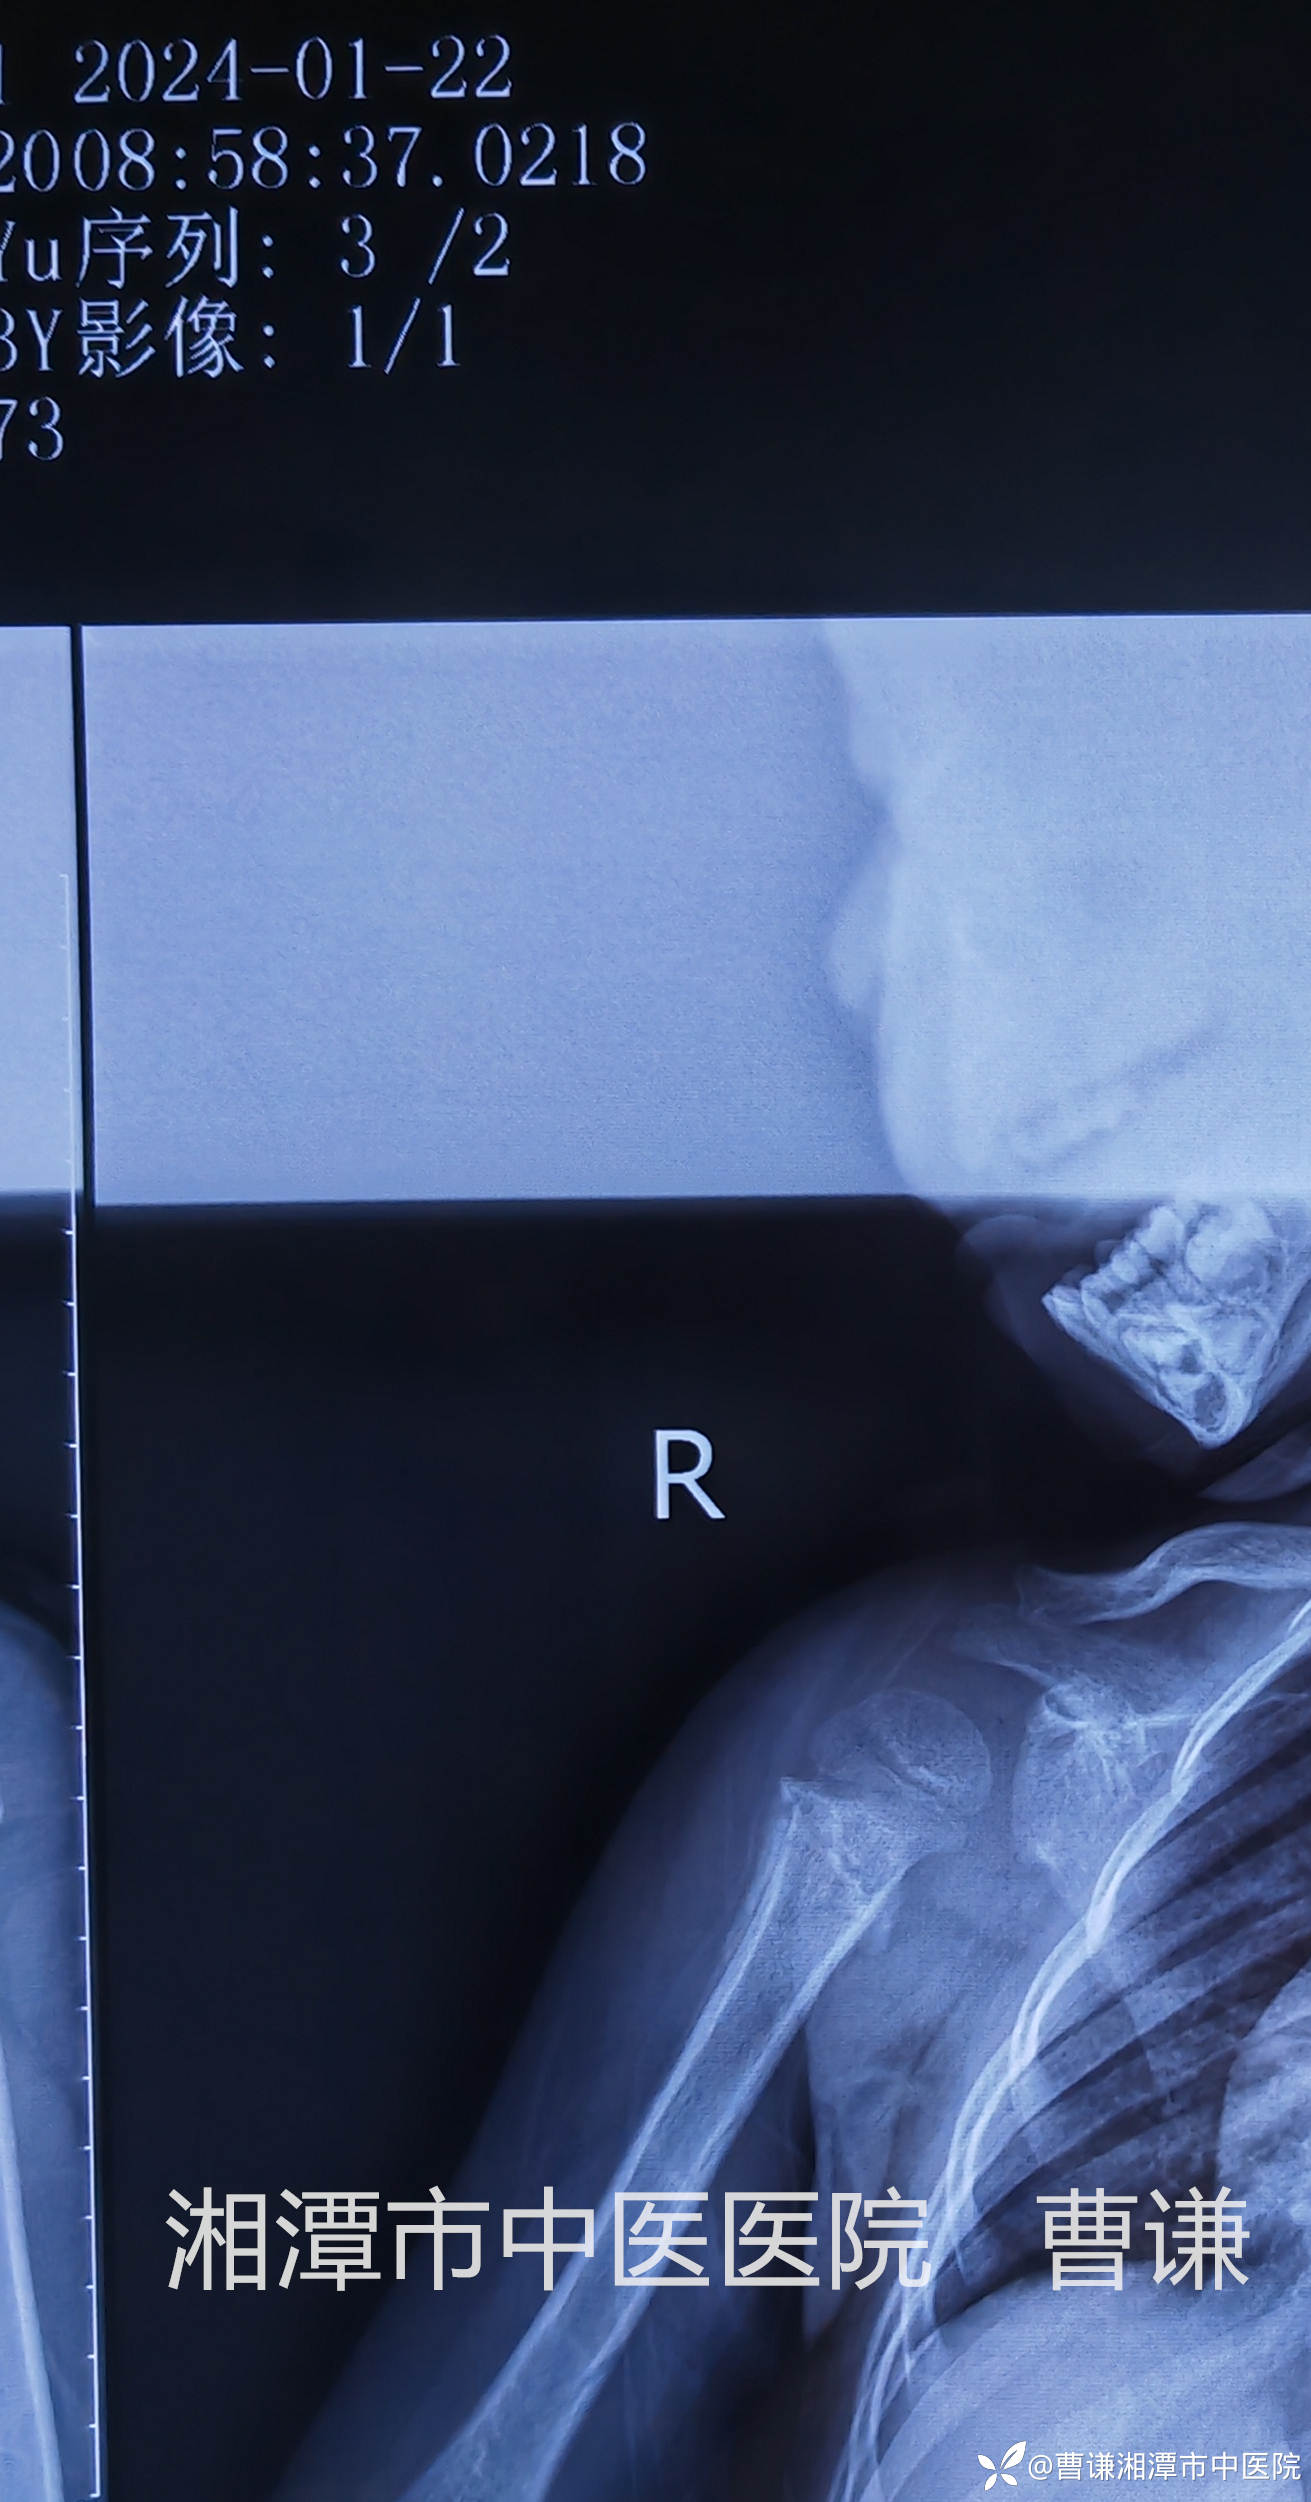

未做刻意复位,稍行屈肘牵引,断端前后对向挤压后予以外敷膏药,四块小夹板外固定,前、后方夹板采用医用胶布经肩关节上方进行紧缩固定,前、外、后方夹板再采用医用胶布经肩关节外侧进行紧缩固定,这样使肩关节与躯体成为一个整体。

再用绷带在外面呈“8”字缠绕紧缩固定,这样的多重固定使骨折端稳定,患者自然不会再诉说疼痛了。

固定完成拍片复查见断端仍然完全错位,肩关节还呈现半脱位的改变。管床大夫赶紧拿着片子给我看,估计心里在嘀咕:主任也是多年的老手了,咋整成这样呢?也可能还在想象我老脸一红,一挥手说:“再整一次!”

我确实是大手一挥,不过是风轻云淡的说:“挺好,继续维持吧!”